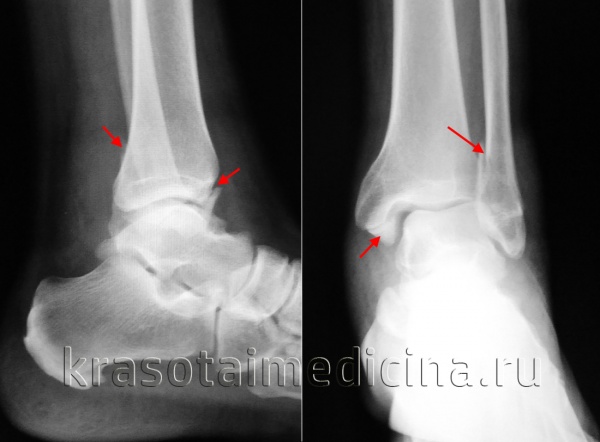

Данные томографии определяют тактику лечения. Так, при переломах заднего отростка (третьей лодыжки) уточняется примерная площадь его суставной поверхности (рис. 1, 2). В случаях, когда площадь отломка превышает 1/3 всей горизонтальной суставной поверхности большеберцовой кости и имеется смещение отломка назад и кверху более 2 мм, больному показан остеосинтез.

(Слева) При рентгенографии голеностопного сустава в передне-задней проекции определяется перелом малоберцовой кости I типа по Салтеру-Харрису (СХ-1) и перелом медиальной лодыжки III типа, обусловленные супинационно-аддукционной травмой.

(Справа) При рентгенографии голеностопного сустава в передне-задней проекции визуализируется перелом СХ-1 дистального отдела малоберцовой кости вследствие супинационно-аддукционной травмы. Ключевыми признаками, позволяющими поставить диагноз, являются отек мягких тканей с латеральной стороны на уровне зоны роста и слабо выраженное ее расширение относительно латеральной части дистальной зоны роста большеберцовой кости. Клинически данные переломы были расценены как переломы СХ-1. (Слева) При КТ в аксиальной плоскости определяется ювенильный перелом Тилло - перелом CX-III, обусловленный супинационно-ротационной травмой. Последней ассимилируется переднелатеральная часть зоны роста, так как данный угол кости подвержен отрывному перелому вследствие тянущего усилия передней нижней межберцовой связки.